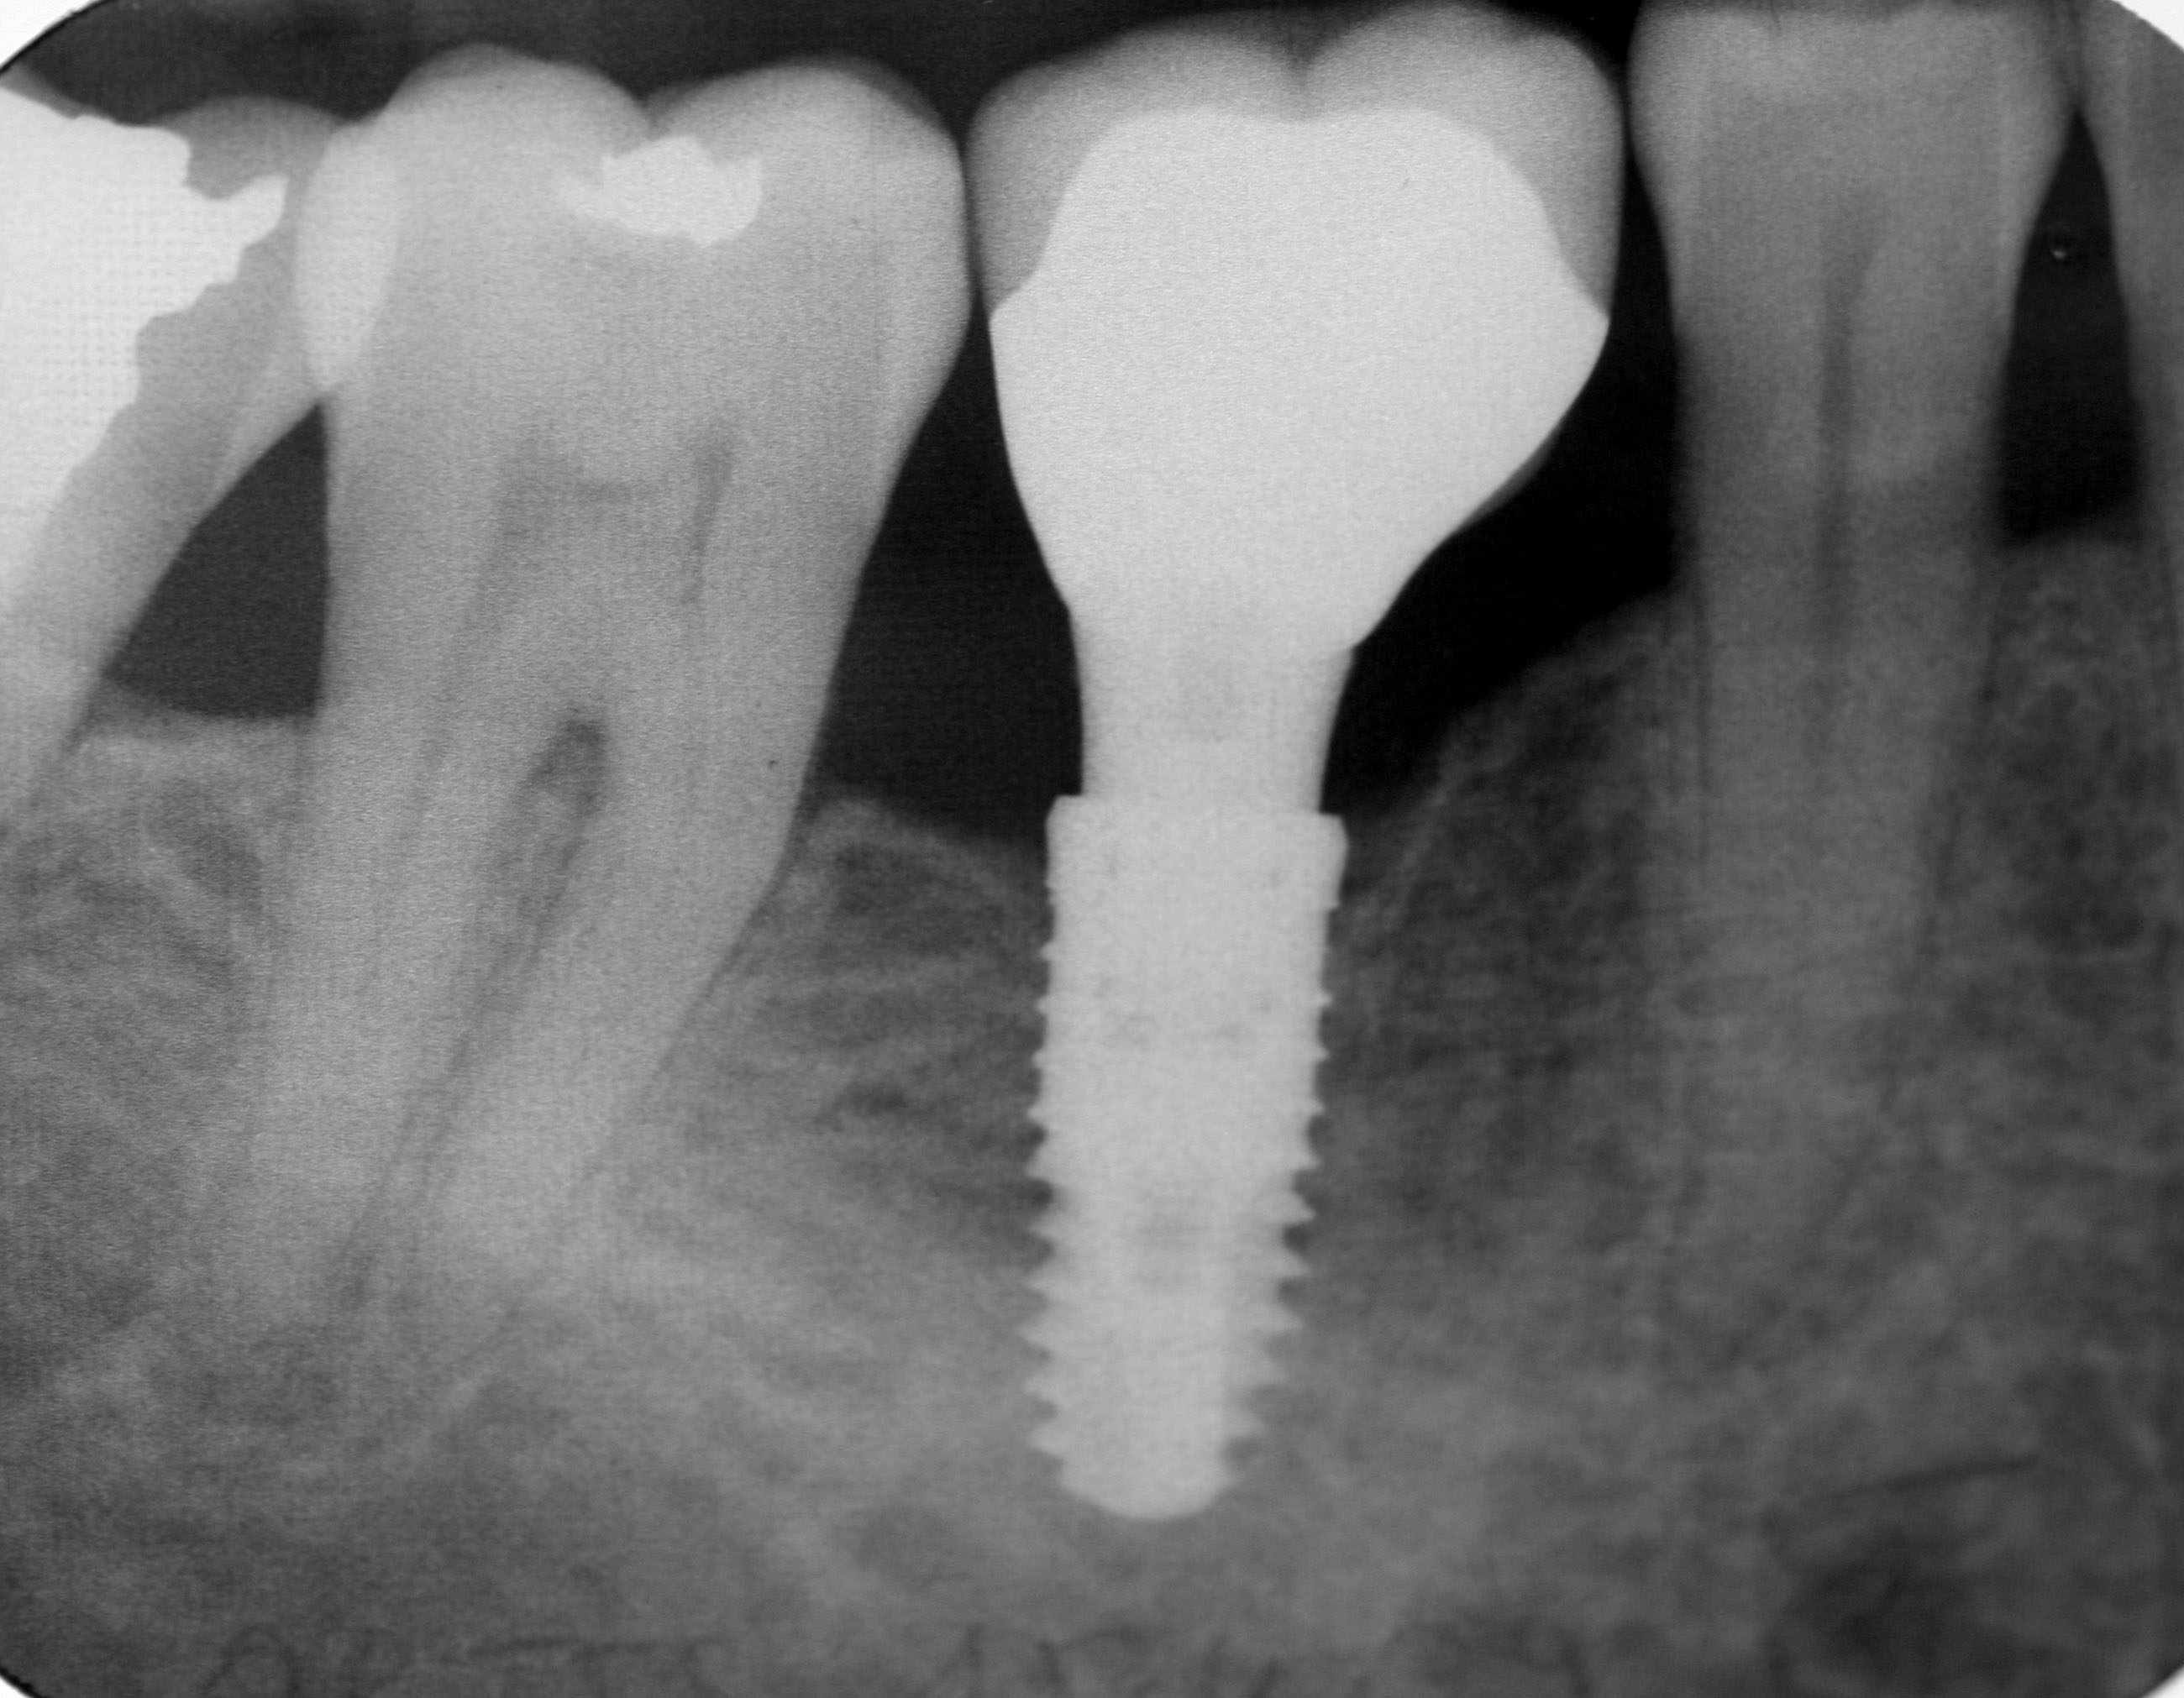

Implant dentaire

Photo d'illustration / DR